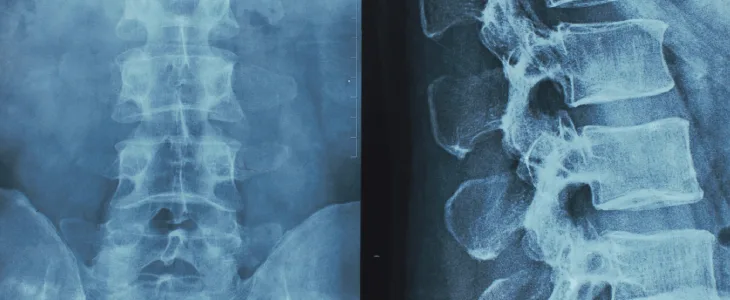

Spinal cord injuries are the result of traumatic damage to the spinal cord, a long bundle of nerves that runs down the vertical axis of the back and conveys messages between the brain and the rest of the body. When an accident damages the spinal cord, the resulting disruption of these messages can result in paralysis. Spinal cord injuries often occur as a result of severe accidents, such as motor vehicle collisions, falls, or sports injuries.

Spinal cord injuries come in two primary types: complete and incomplete. A complete spinal cord injury prevents feeling or movement below the injury level. With an incomplete injury, a patient might retain some feeling or movement below the injury. The impacts of a spinal cord injury can vary depending on where the injury happens along the spinal cord and how severe the damage is. All types of spinal cord injuries can lead to serious problems, like loss of the ability to move, breathe independently, or control the bladder or bowels.